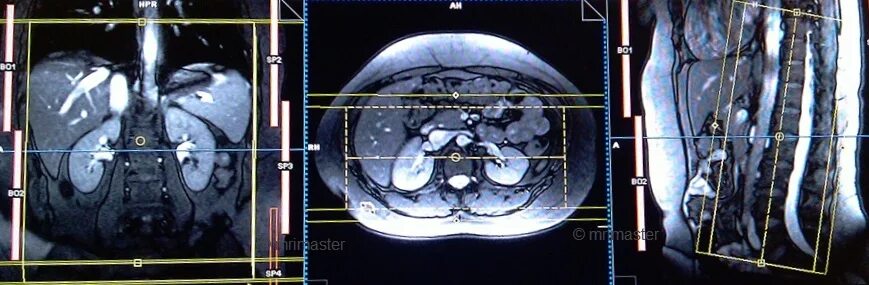

Что входит в мрт забрюшинного пространства